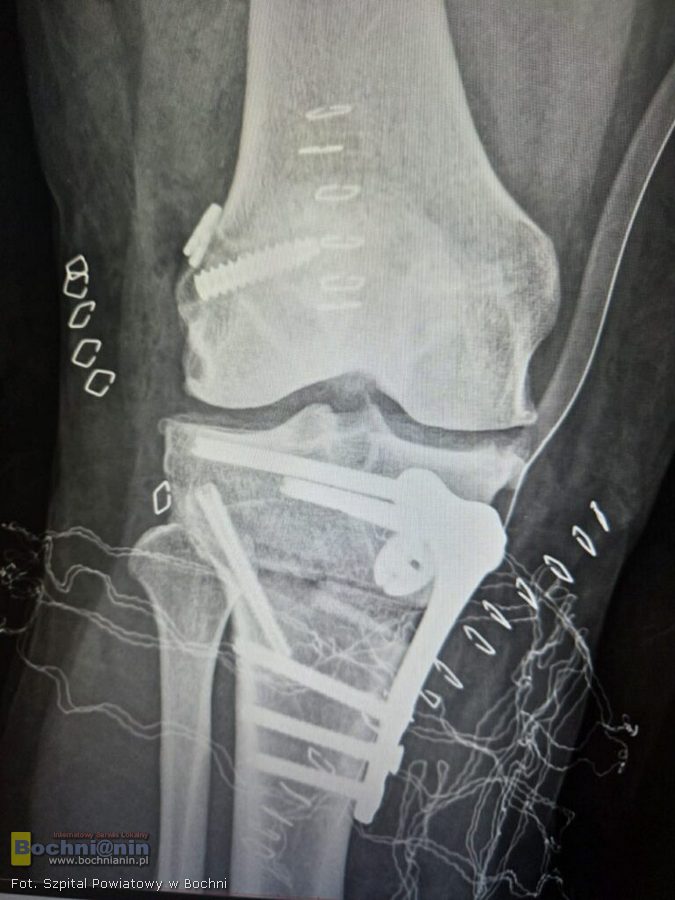

Aby wyeliminować problem konieczne było stworzenie modelu 3D i precyzyjne przemodelowanie kości piszczelowej. Z pomocą przyszedł Jakub Piękoś inżynier medyczny z Warszawy, który zaprojektował komputerowo i precyzyjnie wymierzył przycięcie kości w kilku płaszczyznach. Stworzony model 3D posłużył lekarzom jako przewodnik śródoperacyjny.

– Musieliśmy przyciąć kość w takich kierunkach, aby po wprowadzeniu płytki, zrekonstruowane więzadło zostało utrzymane nawet w przypadku wykonywania ruchów skrętnych. Operacja zakończyła się sukcesem – mówi lek. Mateusz Job, któremu przy wykonywaniu zabiegu towarzyszyli także lek. Michał Budziakowski i lek. Bernard Bukowski.